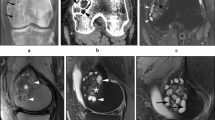

Tumor infiltrating lymphocytes in primary giant cell lesions CD4+ and CD8+ cell infiltration were found in 90% (76 of 85) and 84% (71 of 85) of giant cell lesions, respectively. The number of CD4+ cells ranged between 0 and 93 (mean number, 14.3), whereas that of CD8+ cells ranged between 1 and 184 (mean number, 24.2). Staining patterns of giant cell lesions with CD4+ and CD8+ tumor infiltrating lymphocytes are shown (Fig. 1). There was a weak positive correlation between CD4+ and CD8+ cell infiltration (correlation coefficient, 0.224; p = 0.039). Interestingly, the number of CD8+ cells was lower in aggressive tumors (median, 4.8; interquartile range [IQR], 0.4–13.4) when compared with nonaggressive tumors (median, 15.8; IQR, 4.3–46.3; p = 0.007) (Fig. 2). We then investigated the prognostic value of HLA class I antigen expression in combination with CD8+ T cell infiltration level. Low expression of HLA-B and -C antigens in combination with low CD8+ T cell infiltration was associated with highest risk of tumor aggressiveness (odds ratio [OR],7.81; 95% CI, 1.4–43.5; p = 0.011) when compared with high HLA-B and -C antigen expression and high CD8+ T cell infiltration (Fig. 3).

Representative chromogenic immunohistochemistry staining results of the giant cell lesion tissue microarray are shown for CD4+ and CD8+ tumor infiltrating lymphocytes. The staining was performed using CD8+ and CD4+ specific mAbs according to the manufacturer’s instructions (DAKO, Carpinteria, CA, USA). The results of the staining were calculated by counting the number of stained infiltrating cells in four high-powered fields (×40) in each tissue microarray core. Representative high T cell infiltration and low T cell infiltration are shown. The red arrows point to the stained T cells.

Expression of HLA-A antigens and HLA-B and -C antigens in mononuclear stromal cells were low and heterogeneous in 68% (56 of 83) and 53% (45 of 84) of the tumors, respectively. Similarly, expression of HLA-A antigens and HLA-B and -C antigens in multinucleated giant cells were low and heterogeneous in 65% (49 of 75) and 73% (56 of 77) of the tumors, respectively. There was no difference in the percentage of HLA-A and HLA-B and -C expression in mononuclear stromal cells (percentage difference, 1%; 95% CI, 12%–14%; p = 0.85) and multinucleated giant cells (percentage difference, 2%; 95% CI, −17% to 20%; p = 0.83). Representative staining patterns of giant cell lesions with HLA-A-specific mAb HCA2 and with HLA-B and -C specific mAb HC-10 are shown (Fig. 4). Beta 2-microglobulin expression was low and heterogeneous in 89% (75 of 84) of the mononuclear stromal cells and 51% (39 of 76) of the multinucleated giant cells. Low β2-microglobulin expression level in mononuclear stromal cells was associated with low HLA-A heavy chain (OR, 22.05; 95% CI, 4.00–121.58; p < 0.001) and low HLA-B and -C heavy chain (OR, 13.00; 95% CI, 2.79–60.49; p < 0. 001). Similarly, low β2-microglobulin expression level in multinucleated giant cells of β2-microglobulin was associated with low HLA-A heavy chain (OR, 7.81; 95% CI, 1.4–43.5; p = 0.011) and low HLA-B and -C heavy chain expression (OR, 7.81; 95% CI, 1.4–43.5; p = 0.011). Low expression of HLA-B and -C heavy chain, but not HLA-A heavy chain was associated with aggressive tumors (OR, 4.30; 95% CI, 1.50–12.35; p = 0.005) (Table 2). Similarly, low and heterogeneous β2-microglobulin expression was associated with aggressive tumors (OR, 4.67; 95% CI, 1.29–12.35; p = 0.031). However, when adjusting the data for HLA-B and -C heavy chain expression, we observed no association between low and heterogeneous β2-microglobulin and aggressive tumors (OR, 0.25; 95% CI, 0.03– 2.35; p = 0.383). HLA class II antigens were expressed by mononuclear stromal cells in 69% (58 of 84) of the giant cell lesions; the expression was scored as positive in 26% (22 of 84) lesions and heterogeneous in 43% (36 of 84). HLA class II antigen expression in mononuclear stromal cells was not associated with HLA class I antigen expression in mononuclear stromal cells. However, high expression of HLA class II in mononuclear stromal cells was associated with local tumor invasion to surrounding soft tissue (OR, 6.56; 95% CI, 1.40–30.56; Fisher’s exact test, p = 0.019). HLA class II antigen expression was low or negative in 75 of the 77 samples tested. Two samples were heterogenous and none of them had high expression. HLA class II antigen expression was not associated with HLA class I, or with either CD4+ or CD8+ T cell infiltration.

Representative chromogenic immunohistochemistry staining results of the giant cell lesions tissue microarray are shown for the five immunologic markers HLA class I HLA-A heavy chain (stained using hydroxycarboxylic acid receptors (HCA2) mAb), HLA class I HLA-B and -C (stained using HC-10 mAb), HLA class I β-2 using microglobulin (β2m) light chain (stained using namb-1 mAb), HLA class II (stained using lgii-612.14 mAb), and B7-H3 (stained using B7-H3-specific mAb 1027). Each tissue microarray core was scored as low, heterogeneous, or high if the percentage of the stained area lesion was less than 25%, 25% to 75%, and greater than 75%, respectively.